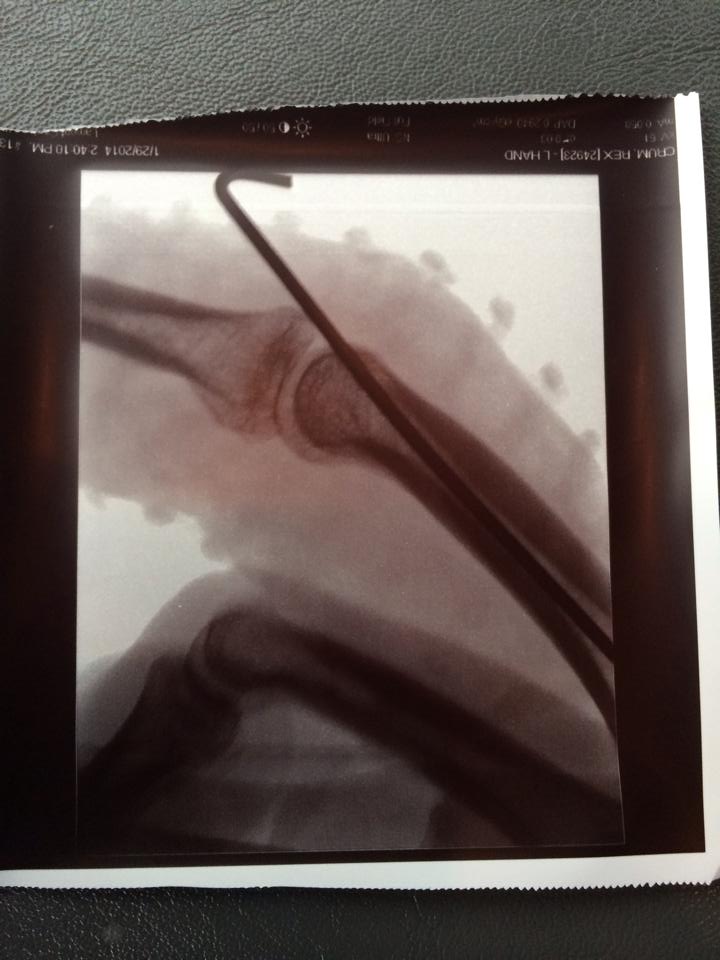

Jumping forward a bit from there, I ended up in a hospital emergency room. Then at the office of a hand specialist. X-rays showed a small fracture of my ring finger, with the position of my ring likely keeping the break from being worse. But the real money shot was what the doctor found when he looked at my middle finger.

Part of the bone just above the second knuckle had been shaved off. The doctor said a simple splint would be enough to help that injury heal. But thanks to the door, the second joint on that finger was more out of whack than the final score of this year’s Super Bowl…won 43-8 by my aforementioned Beloved Seattle Seahawks.

Watch: What It’s Like To See Your Team Of Almost 40 Years Win Its First Super Bowl

The doctor determined the best way to fix that was to drill a long metal pin into my finger to stabilize the joint and let it heal over the next month or so. And that’s how I ended up with the mini-coat hanger hook sticking out of my skin.